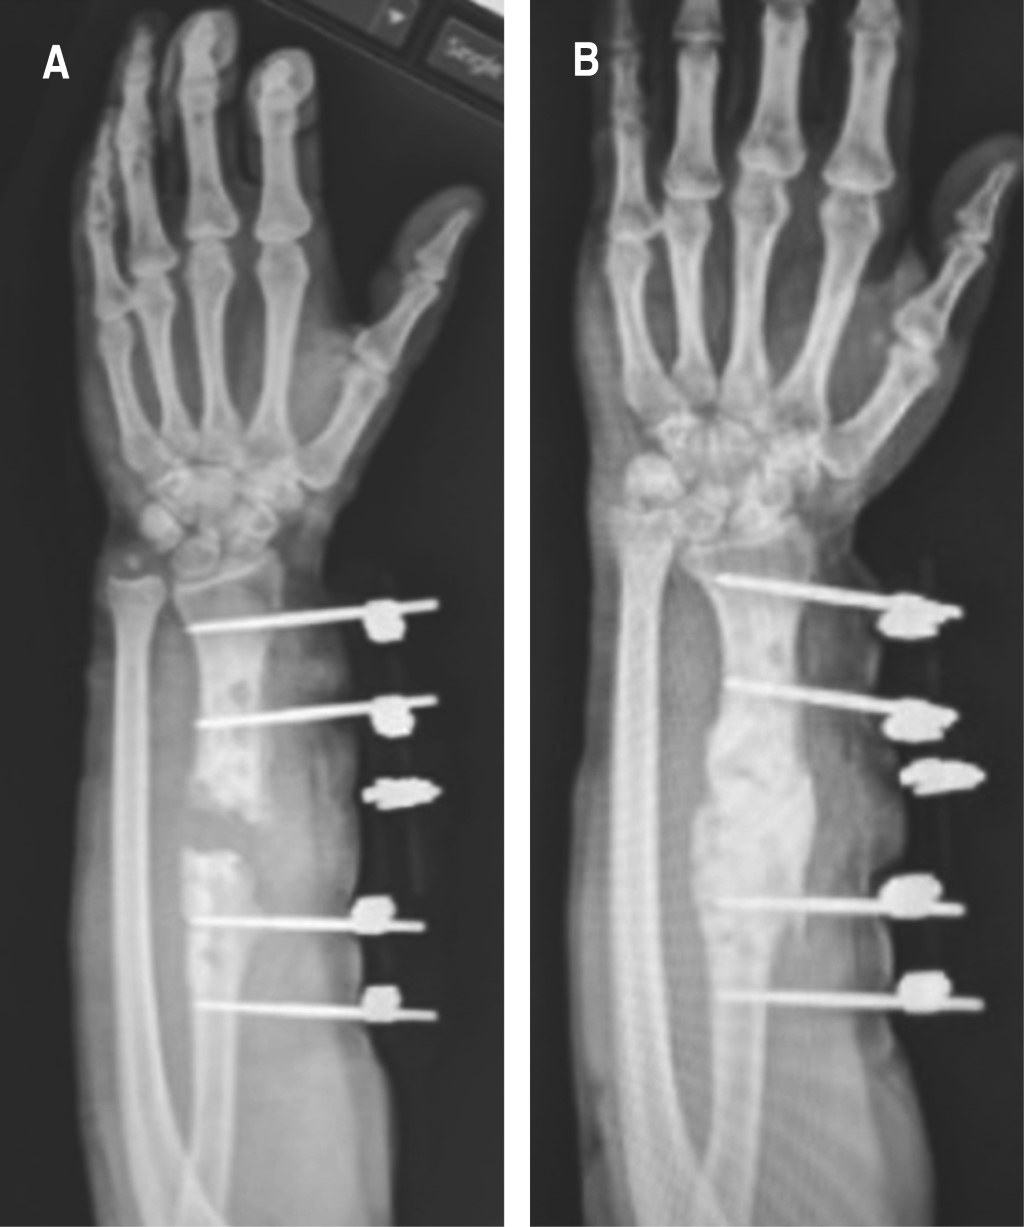

Después de 16 semanas de seguimiento con normalización de cuenta leucocitaria (< 4,000 mm3) y reactantes de fase aguda negativos (VSG < 10 mm/h, PCR < 5 mm mg/l), que traducen infección remitida, se decide realizar Masquelet fase 2. Primero posicionamos al paciente en decúbito lateral, y con ayuda de control fluoroscópico se posiciona una aguja Jamshidi 11 G x 10 cm en la cresta iliaca posterosuperior en la sección anatómica del íleon 6, además, de manera percutánea se procede a realizar aspirado de médula ósea, del que se extrae 1 ml, al girar el bisel y retraer la aguja por cada mililitro de aspirado, con lo cual se evita aspirar cantidades mayores a éste, debido a la dilución por sangre periférica que disminuye la concentración de células madre mesenquimales (MSC, por sus siglas en inglés), hasta tener tres jeringas de 10 ml.11-13 En el transoperatorio, al hacer escarificación y hueso sangrante, se determina una pérdida ósea de 7 cm, realizamos toma y aplicación de dos bloques de cresta iliaca de 2 y 5 cm, respectivamente, y colocamos LCP de 3.5 de radio con 12 orificios, se colocaron cuatro tornillos proximales, dos al injerto y cuatro distales, con lo que nos aseguramos de obtener una osteosíntesis lo más rígida posible. El injerto restante se prepara en pequeños fragmentos de 3 mm. Finalmente, se procede a realizar mezcla del aspirado de médula ósea con el aloinjerto óseo de cresta, con el cual se rellenó la pérdida restante (Figura 3).

Gracias al seguimiento del paciente a uno, dos, tres, seis, ocho, 10 y 12 meses se obtuvo evolución satisfactoria tanto clínica como radiográficamente. Apreciamos puentes óseos en los extremos del aloinjerto de cresta a partir del tercer mes, por lo que se indicó rehabilitación con ejercicios isométricos, con carga parcial progresiva, mejorando la formación del callo óseo en el control a los seis meses, por lo que se indicó trabajo normal de la extremidad. Observamos regeneración ósea total a los 10 meses (Figura 4). En la actualidad el paciente se encuentra con función de extremidad conservada con una puntuación de 100 puntos en la escala modificada de muñeca de mayo.14